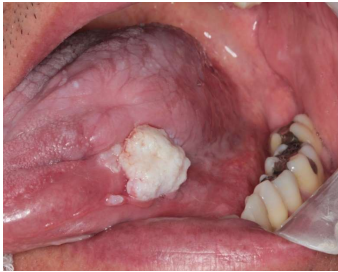

Caso clínico II - Paciente do sexo masculino, 54 anos de idade, procurou atendimento odontológico devido à lesão branca, assintomática, não raspável, localizada em língua e com 4 meses de evolução. Durante a anamnese, relatou ser tabagista e etilista há 22 anos.

Os diagnósticos clínicos mais prováveis para os casos clínicos I e II, respectivamente, são: